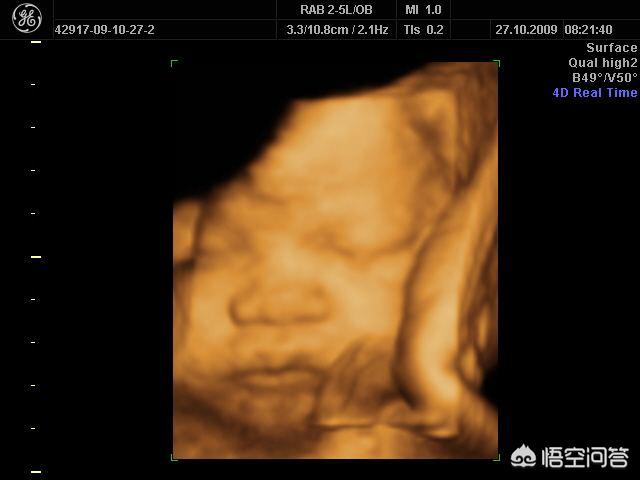

宝宝四维彩超和出生后模样像吗?皮肤是白是黑在四维彩超图片上是看不出来的。必竟是隔着皮肤。肌肉组织。羊水拍的照片。而且拍四维彩超孩子是闭着眼睛的。眼睛大小。鼻子的型状。嘴巴型状。和出生后有很大区别。但是四维彩超上孩子的脸型。和出生后还是很像的。

孩子是26周拍的四维。图片上。孩子胖胖的。图片面部颜色偏浅。一只手托着一侧面部。像是在安安静静的休憩。特别可爱。

生下来。脸型和四维彩超上一模一样。皮肤白。大眼睛。现在一直保存着那张四维彩超图片。直到现在有时候会把那张四维彩超图翻出来看一看。比一比。现在孩子都就么大了。但是从图片上还是一下子就能看出来是他。现在小脸的轮廓还是和在妈妈肚子里时没什么两样。可爱的很。

你要是想从四维彩超图片上看孩子的样子。先让医生看看胎儿所处的位置。如果能把孩子面部拍正最好。这样就可以看到孩子的基本面部型状。至于眼睛大小。鼻子是不是好看。嘴巴的大小。还是等生出来再好好看吧!